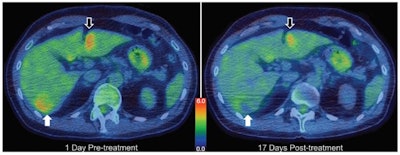

Treatment planning, modeling, and example results from a 50-year-old man with diffuse multilobular hepatocellular carcinoma in segment VI. Axial F-18 FDG PET/CT images obtained one day before (left) and 17 days after (right) treatment. Total lesion glycolysis of target tumor (white arrows) decreased by 36.4%, whereas there was no substantial change over the volume of a similarly sized tumor that received drug but no focused ultrasound (black arrows). Color bar indicates standardized uptake value. Images courtesy of Michael Gray, PhD, et al, Radiology."A key objective in developing the planning model was to not only validate the safety and feasibility of noninvasively triggered drug delivery in oncology, but to do so in a way that would enable large-scale adoption and deployment of the technique if successful," explains first author Michael Gray, PhD, senior research fellow in Clinical Therapeutic Ultrasound. "We hypothesized that neither expensive nor invasive thermometry would be necessary for mild hyperthermia-based treatments employing noninvasive ultrasound for targeted heating."

To assess therapeutic response, the team imaged all participants before and after treatment using contrast-enhanced MRI and CT and also FDG-PET/CT. In the first patient, PET revealed a 36.4% reduction in total lesion glycolysis of the target tumor, whereas there was no substantial response in a similarly sized tumor that received drug but no focused ultrasound. In six of the 10 participants, partial responses were seen after just one treatment cycle.